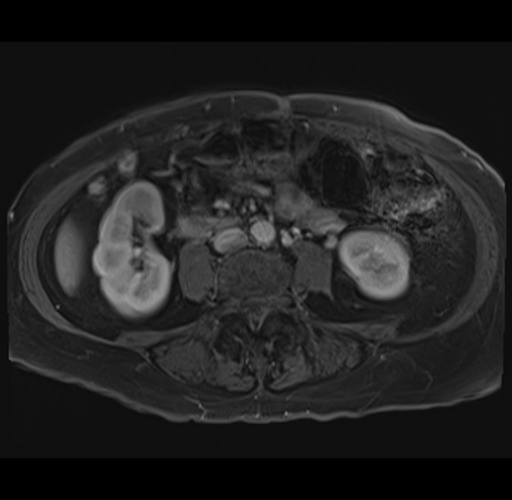

MRI T1

Imaging analysis